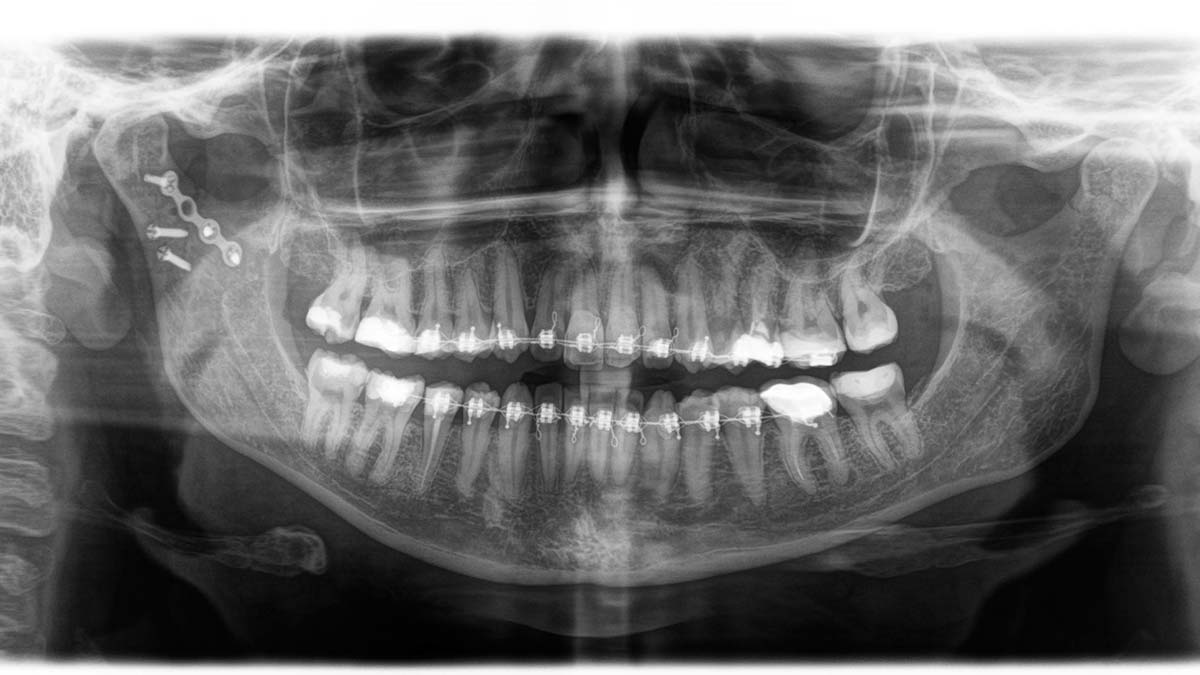

Ağan şöyle konuştu: “Eskiden diş acillerine ev ya da trafik kazaları sonucu travma hastaları sık gelirdi. Şimdi acile gelen çene ve diş travmalarının çoğunluğu elektrikli skuter kullanımına bağlı oluyor. Son yıllarda bunlarda büyük bir artış görüyoruz. Travmanın geliş açısına bağlı olarak en çok ön dişlerde kırıklar oluyor. Kask kullanımı tabii ki kafa travmalarının önüne geçilebilir. Ama skuterlerde direkt öne doğru düştükleri için, çene ve burnun üstüne düşme ihtimalleri çok daha fazla. Onda da çene geriye doğru gittiğinde eklem bölgesinde basılar ya da kırıklar oluyor. Dolayısıyla çene koruyucusunu da dahil olduğu bir kask kullanılması gerekiyor. Bisiklette kullanılan kasklar çene ya da burun travmaları için tam da önleyici olur diyemeyiz.”

Geçici yüz felci yaşadığını ve 7 ayının kabus gibi geçtiğini anlatan Gümülcinelioğlu şunları anlattı: “Skuter aslında çok sıklıkla kullanmıyorum. Üçüncü kez kullanmıştım, eve acil dönmem gerekiyordu. Yürümek yerine skuter kullanayım dedim. Sokak köşesinde dönemeçten hemen sonra bir restoran vardı. Restoranın masaları nedeniyle yavaşlamıştım ama döndüğüm an önümdeki mazgalı fark etmedim. Tekerlek o mazgala girdi. Öne doğru savruldum ve çenemi çarptım. Çenem, burnum, bütün yüzümü yere çarptım. Olayın sıcağıyla başta anlamadım. Çene kemiğim iki taraftan kırılmış. Çok büyük bir cerrahi ameliyat geçirdim. Ameliyat öncesinde dişlerime tel takıldı. Çünkü lastikle çenemi oturtmaları gerekiyordu.

Ameliyatın yapıldığı yerden yüz sinirleri geçtiği için, sağ tarafımda yüz sinirlerimde geçici yüz felci oluştu. Gözüm kapanmıyordu, güldüğüm zaman ağzım hareket etmiyordu. Çiğneme, yemek yiyememe bir tarafa, ağrılarım dayanılmazdı. 6-7 ayı buldu iyileşmem. Sağ tarafım, ameliyat sonrası başka bir ben oldu. Bu olaydan sonra uygulamayı hemen sildim ve çevremdeki insanlara da başıma geleni anlatıp kullanmamalarını öneriyorum.”